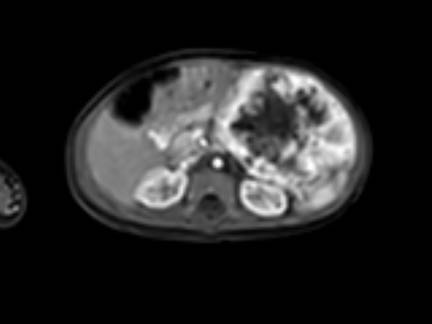

Đây là hình ảnh T1W axial có tiêm gadolinium với kỹ thuật xóa mỡ.

Hình ảnh cho thấy sự bao bọc của các mạch máu.

Lưu ý sự lan rộng của khối u ra phía sau động mạch chủ, đẩy động mạch chủ ra xa cột sống (mũi tên).